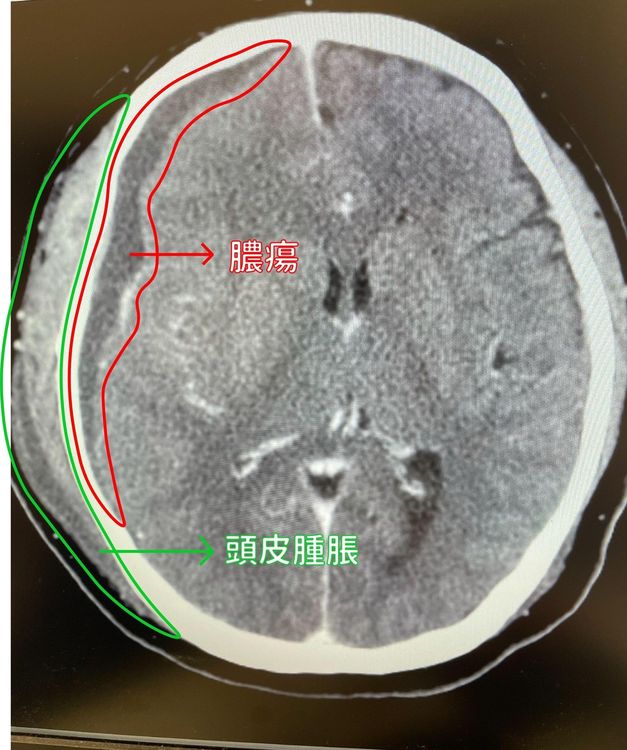

該名工程師病程進展快速,引發敗血性休克,顱內膿瘍、呼吸衰竭。中醫大提供

巫智潁表示,由於該病患病程進展快速,引發敗血性休克,顱內膿瘍,呼吸衰竭,於加護病房治療期間,施予經鼻氣管內管置入,後線抗生素及升壓劑治療,並以開顱併內膿瘍清除手術。經2個月治療之後,患者不僅脫離呼吸器沒有插管,意識也恢復清醒,手腳活動無礙,眼睛及頸部腫脹消失,唯膿瘍跑到眼睛造成視力模糊的後遺症。